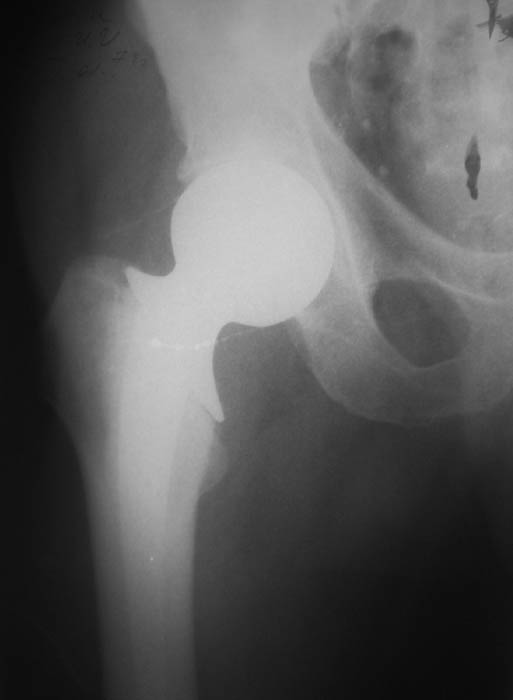

Мужчина, 77 лет. В 2000 г. по поводу субкапитального перелома шейки бедренной кости произведена операция эндопротезирования головки. На последних рентгенограммах обнаружена протрузия головки эндопротеза.

В настоящее ведет активный образ жизни, продолжает работать.Предполагается замена протеза на тотальный ревизионный. Интересуют предложения по восстановлению костной массы вертлужной впадины.Заранее благодарю!С уважением,А.В.ВладзимирскийДонецкий НИИ травматологии и ортопедииДонецк, Украина